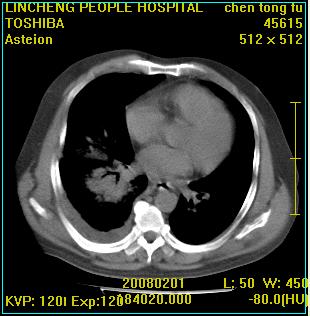

患者,男性,62岁。主因头晕,发热,咳嗽6天,高热达39度,esr19mm/h,wbc 3.9×10 9/l

大叶性肺炎并胸膜炎

右肺大叶性肺炎,胸腔积液。建议痰检。

实变区见空气支气管征,支气管通畅,考虑为大叶性肺炎,右侧少量胸水

1)考虑为:右肺感染性病变。建议:抗炎治疗复查。2)右侧少量胸腔积液。

考虑为右肺大叶性肺炎,胸腔积液,建议必要时纤维支气管镜检查,以排除肿瘤性病变。

右肺炎症并右侧胸腔少量积液。

考虑为右肺大叶性肺炎伴少量胸腔积液,建议复查,如病变不吸收或吸收不明显,建议纤维支气管镜检查,除外细支气管肺泡癌的可能。

右侧大叶性肺炎,右侧少量胸腔积液.